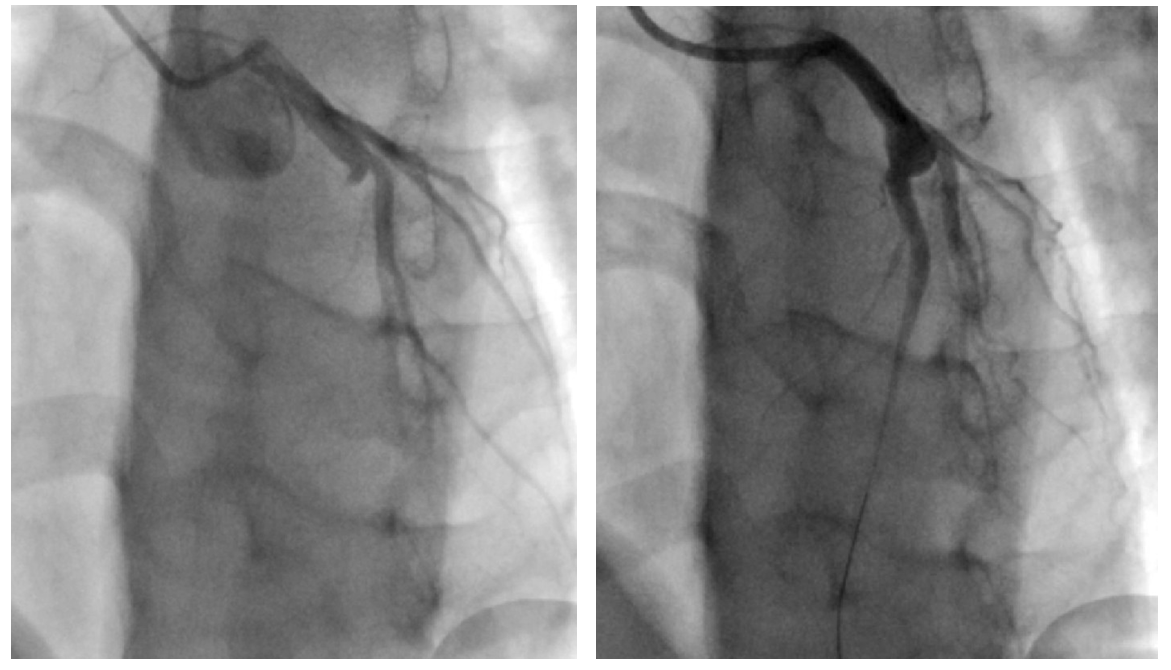

遂立即急诊行冠状动脉造影

检查,结果显示前降支自近段闭塞(图3左),在反复抽吸血栓,冠脉内给予尿激酶

等药物后,冠状动脉血流得到改善,再次造影显示前降支近段存在一个巨大瘤样扩张(图3右)。行血管内超声

图3左提示前降支自近段闭塞;图3右是反复抽吸、冠脉内给予溶栓药物后可见前降支近段有一个冠状动脉瘤